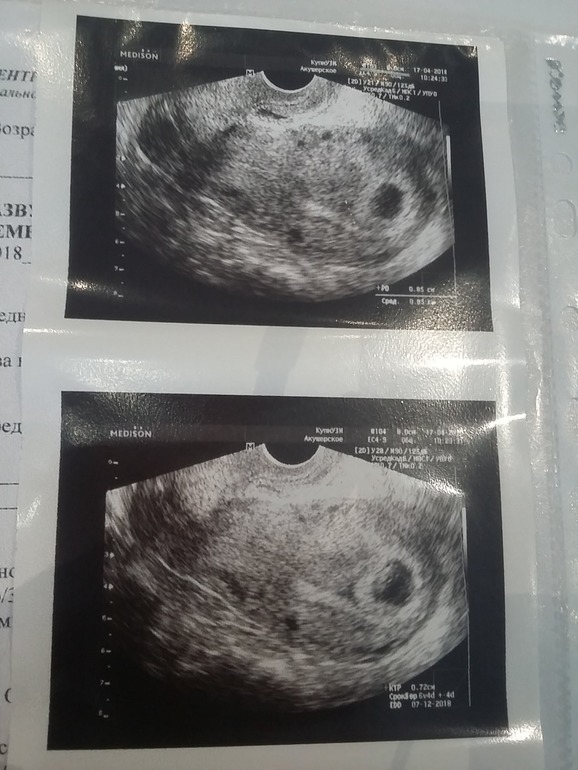

Результаты Узи 6 нед и 4 дня

Вопросы про УЗИ, обследования и анализы: что, где, как, когда?Ситуация такая.. Сегодня утром увидела маааленькую капельку крови на бумаге. На прокладке все чисто. Никаких намеков. Я перепугалась и поехала на узи (плавновое узи у меня стоит на след. среду в жк). И Вот результат сегодняшнего узи.

Странно то, что мне сейчас ставят гематому. Но когда я была на узи 1.5 недели назад, у меня была миома. Сейчас эта узист говорит, что никакой миомы она не видит.

Вот мое прошлое заключение с узи

Видимо какой то врач ошибается? Или как?